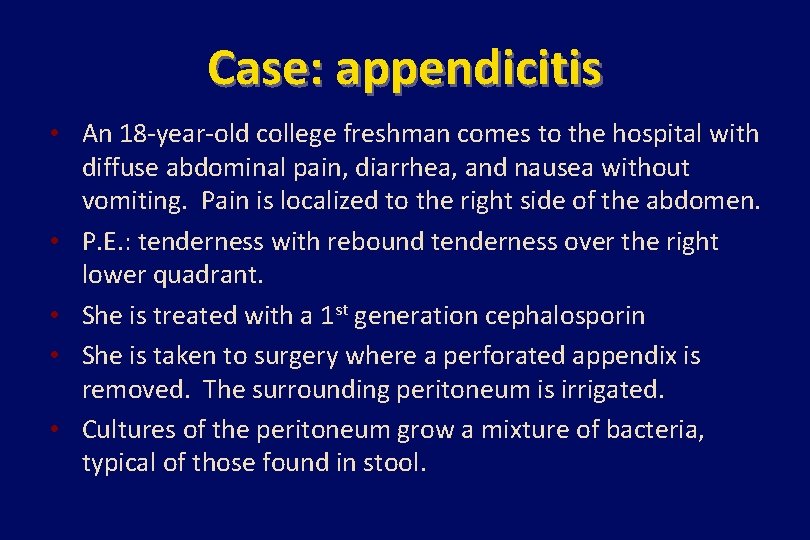

Case: appendicitis • An 18 -year-old college freshman comes to the hospital with diffuse abdominal pain, diarrhea, and nausea without vomiting. Pain is localized to the right side of the abdomen. • P. E. : tenderness with rebound tenderness over the right lower quadrant. • She is treated with a 1 st generation cephalosporin • She is taken to surgery where a perforated appendix is removed. The surrounding peritoneum is irrigated. • Cultures of the peritoneum grow a mixture of bacteria, typical of those found in stool.

Case (continued) • On post-op day #2, her temp spikes to 38. 6°C. • Blood cultures obtained preoperatively grow E. coli. • She completes a 7 -day course of cefazolin and improves. Since she has no further symptoms and follow-up blood cultures are negative, the antibiotic is stopped. • 36 hours later, her temperature is 38. 8°C and she feels diffuse pain over the site of the appendectomy. • A CT scan of her abdomen reveals a retroperitoneal abscess.

Case (continued) • The abscess is drained, and cultures of pus from the drainage grow Bacteroides fragilis. • She is treated with ampicillin-sulbactam for 14 more days. Her drain is pulled after 7 days, and she has an uneventful recovery.